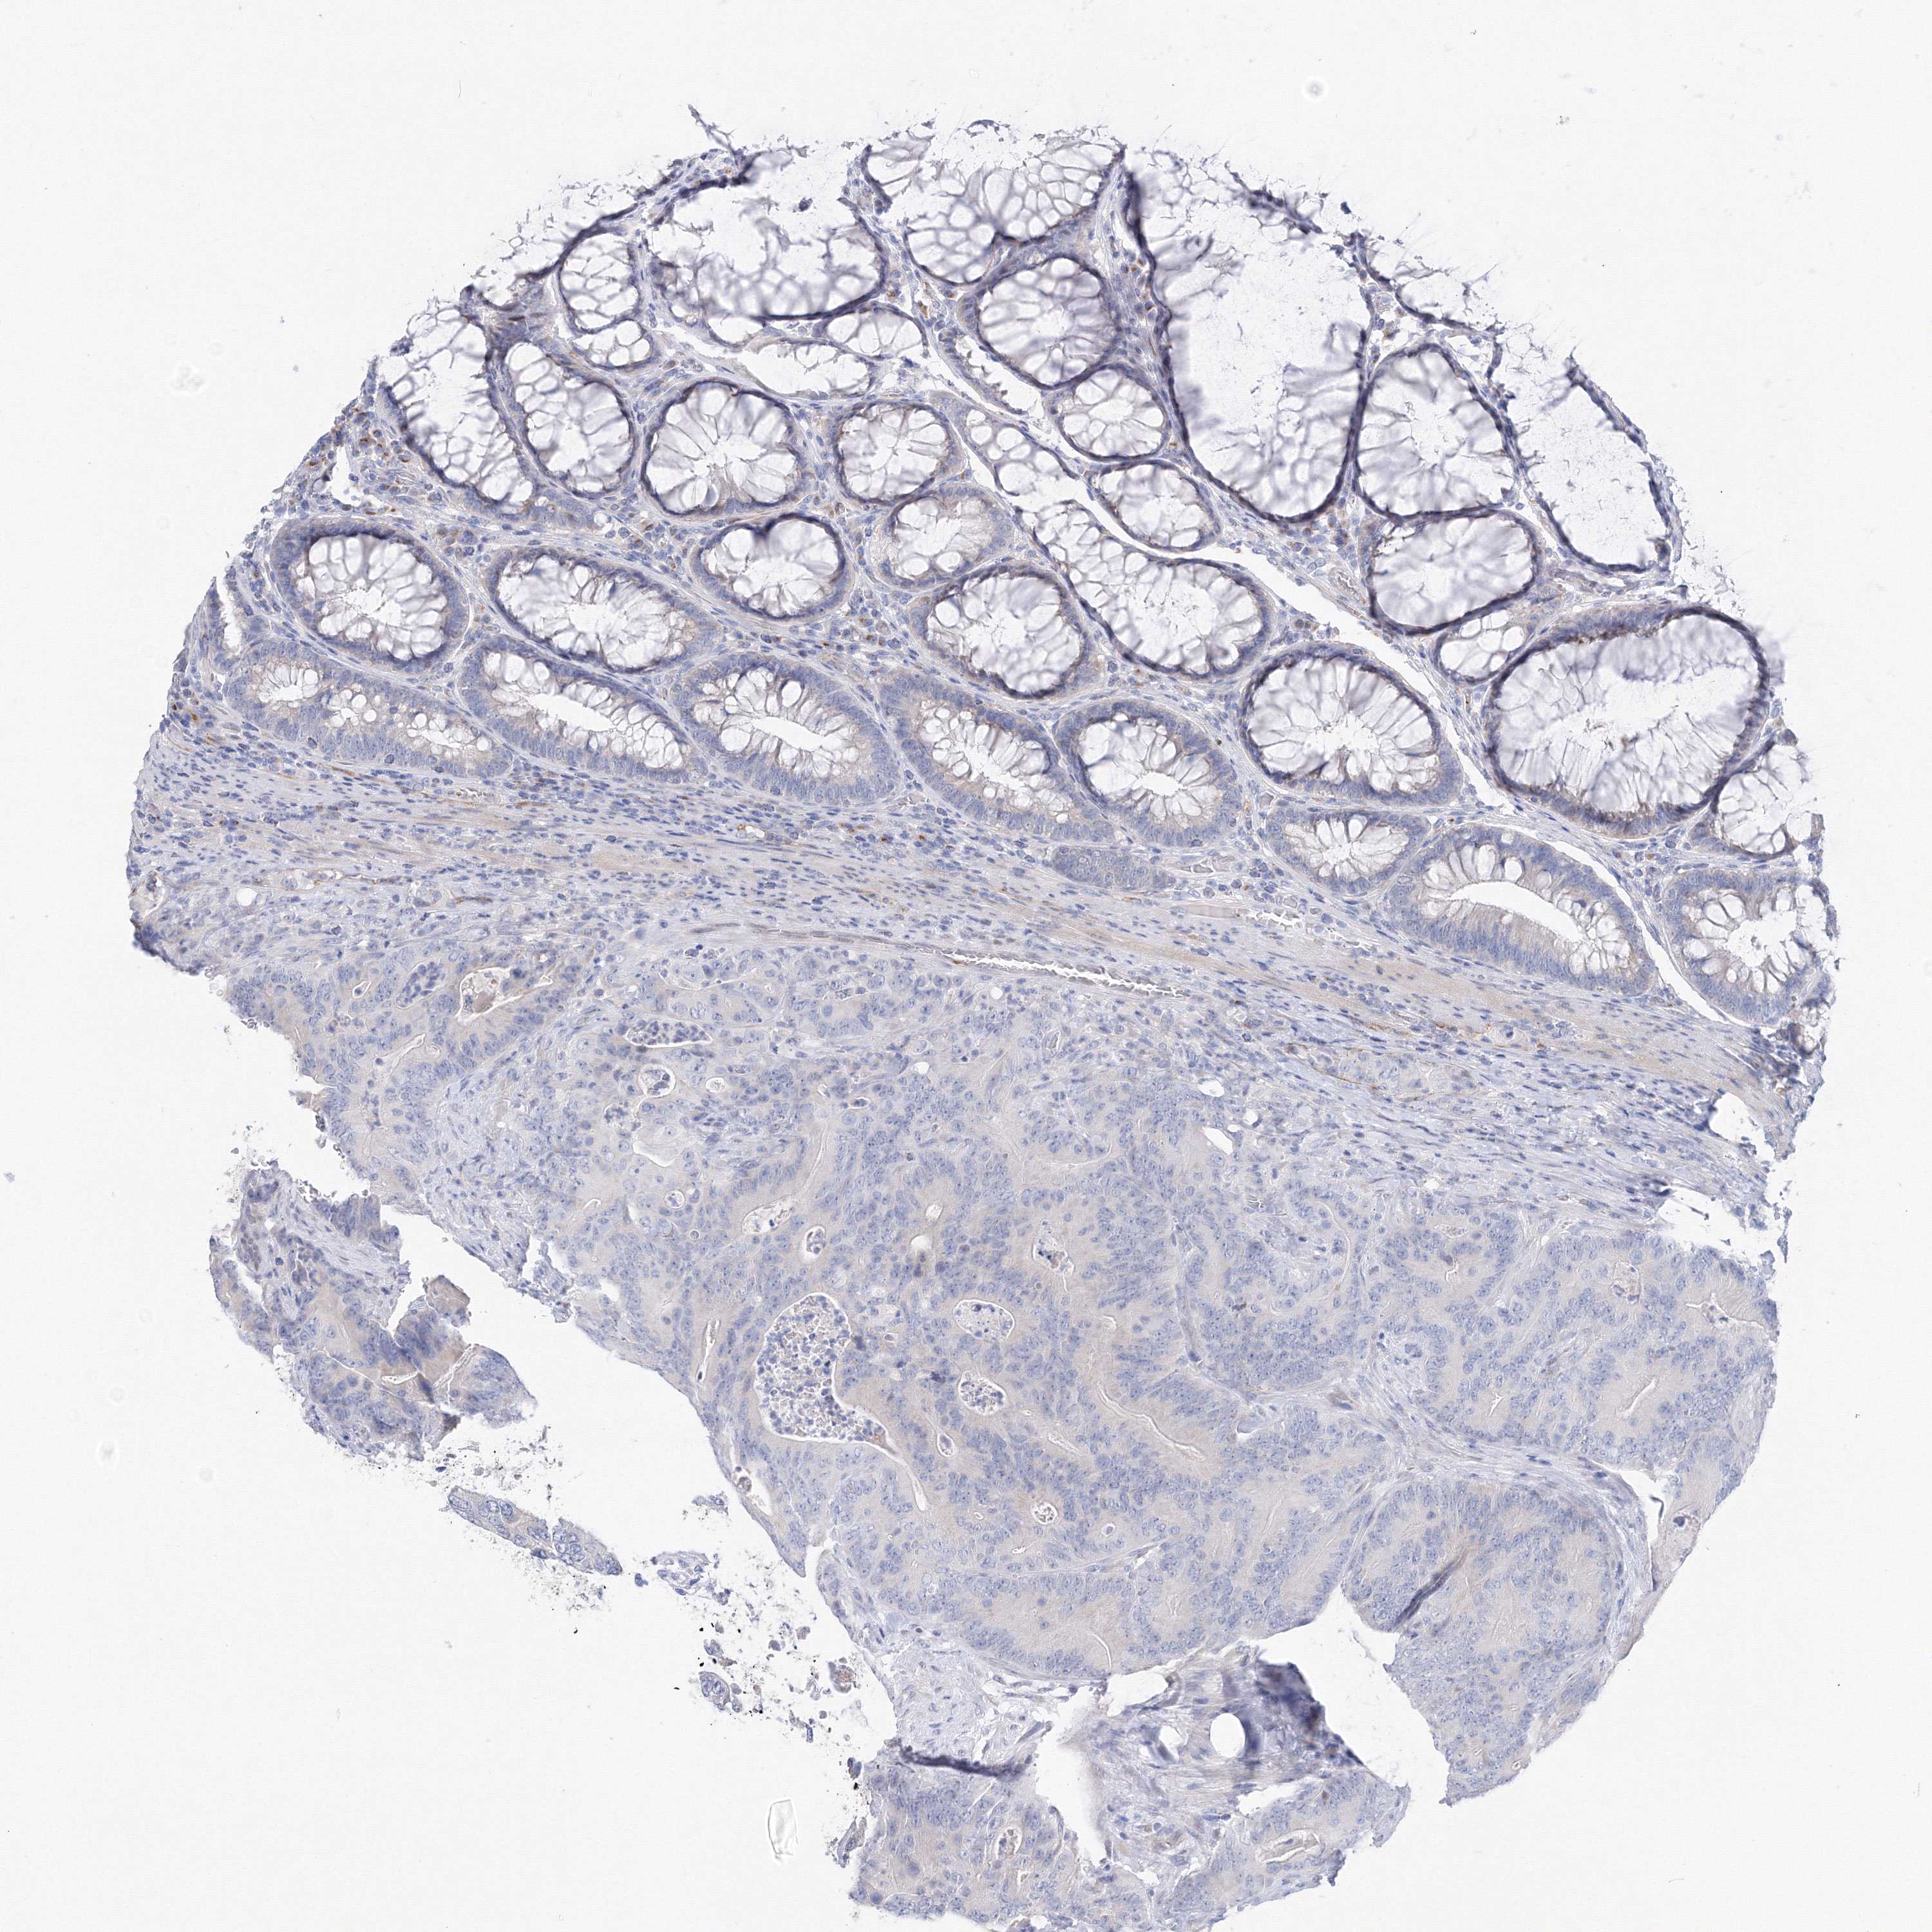

ANTIBODIES

AND

VALIDATION